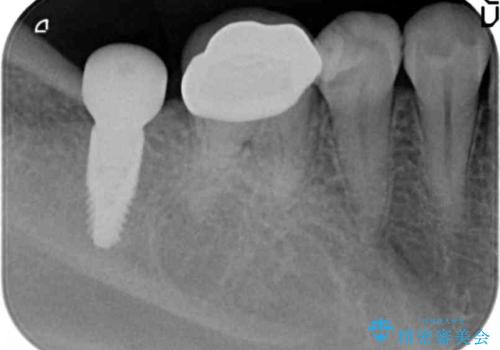

奥歯のインプラント治療

- 右下の奥歯を虫歯で喪失しそれ以来よく物が噛めず、改善を求めて来院されました。

入れ歯かインプラント治療のご提案を行い、よりしっかりとかめるインプラント治療を希望されました。

骨との結合する期間が早く、大きな咬合力にもしっかりと耐えることのできるストローマンインプラントを用いた咬合機能回復を計画します。

- 44万円(ストローマンインプラント・チタンカスタムアバットメント・仮歯・フルジルコニアクラウン)費用は治療当時の料金となります